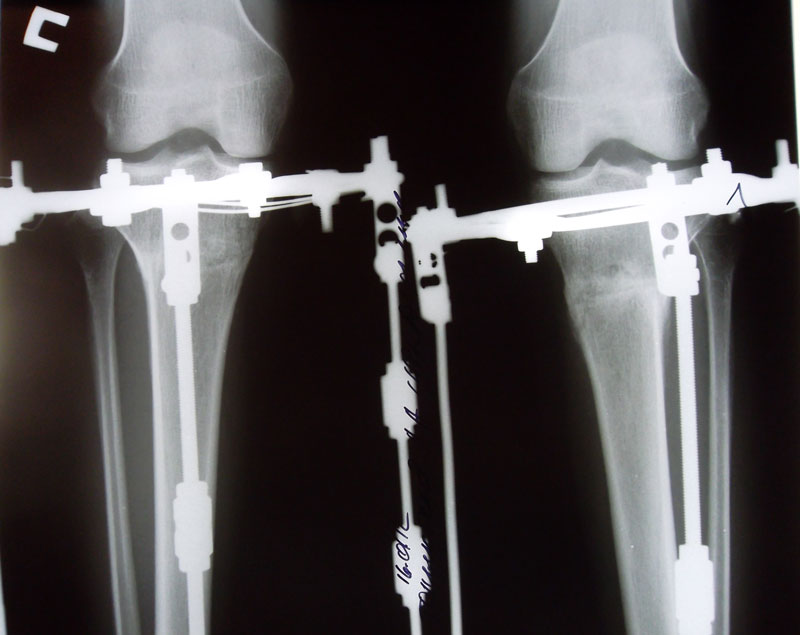

Пациентка Solnyshko

Аппаратная жизнь 83 дня - закончилась. Сегодня сняли аппараты.